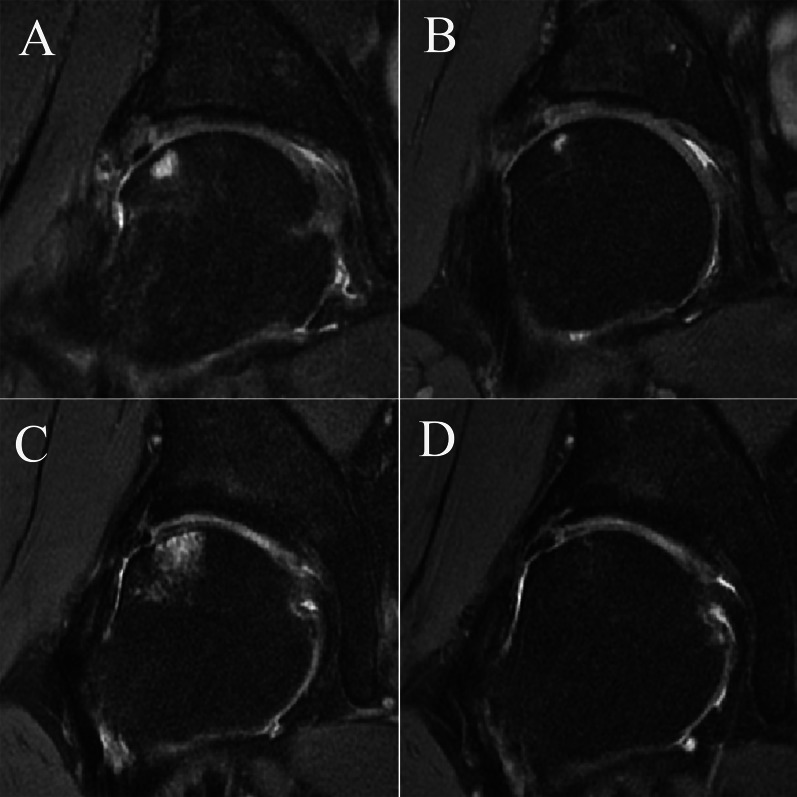

Background: Postoperative femoral head cartilage injury (FHCI) is a rare condition that can be observed in a certain proportion of patients undergoing hip arthroscopy. However, the prevalence and associated factors of FHCI, and the effect of this condition on clinical outcomes still remain unknown.

Patients and methods: Consecutive patients who were diagnosed with femoroacetabular impingement syndrome (FAIS) and labral tear and underwent hip arthroscopic treatment in our institute between July 2020 and July 2021 were retrospectively evaluated. Supine anteroposterior hip radiographs, cross-table lateral radiographs, magnetic resonance imaging (MRI), and computed tomography (CT) were obtained preoperatively. Postoperative MRI, at least 6 months after arthroscopy, was performed. Postoperative FHCI was evaluated by two surgeons through MRI. Preoperative patient-reported outcomes (PROs) including visual analog scale (VAS) for pain, and modified Harris Hip Score (mHHS) before surgery and at final followup were obtained.

Results: A total of 196 patients were included. Postoperative FHCI was identified in 21 (10.7%) patients. The intraobserver reliability of the observer A and B for detecting postoperative FHCI using 3.0-T MRI was high (k = 0.929, and k = 0.947, respectively). The interobserver reliability between the two observers for detecting FHCI using 3.0-T MRI was high (k = 0.919). There was no significant difference in preoperative and postoperative mHHS, VAS, and percentage of patients who surpassed minimal clinically important difference (MCID) and achieved patient acceptable symptom state (PASS) between patients with and without postoperative FHCI (P > 0.05).

Conclusion: Although postoperative FHCI was observed in 10.7% of patients, which was associated with larger labrum, this condition did not result in inferior clinical outcomes. Level of evidence IV, retrospective case series. Trial registration The Chinese Clinical Trial Registry approved the registration (ChiCTR2200061166). The date of registration is 2022-06-15.